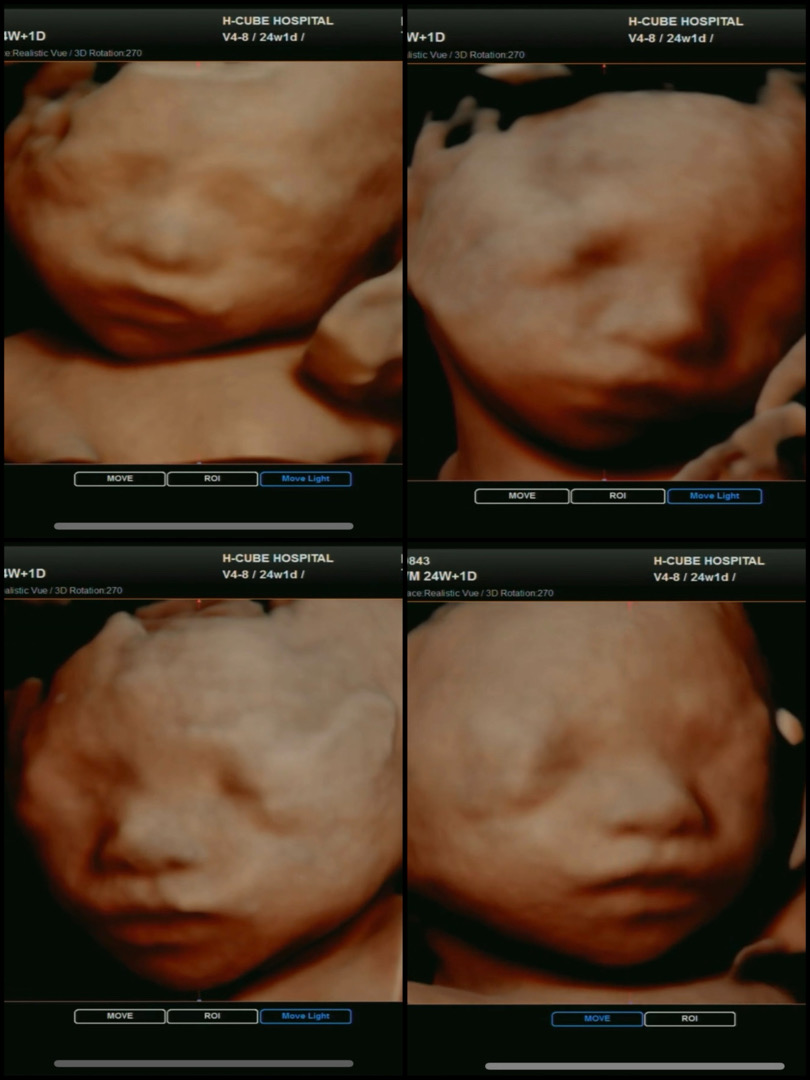

입초 찍고왔어요!

입초 찍으러 가는 날 계속 말을 걸었던거 같아요 이따가 엄마랑 사진찍으러 가는데~ 찰칵! 하면 잠깐만 얼음!!하고 있어줘~ ㅋㅋㅋㅋㅋㅋㅋ 다행히 협조적이여서 정면, 좌, 우 다 보고왔네옄ㅋㅋㅋ

요건 24주1일차에 본 입체초음파예요! 아직 살이 안올랐는데 28주정도 지나서 보는분들은 통통하니 더 이쁘다고 하더라구요!